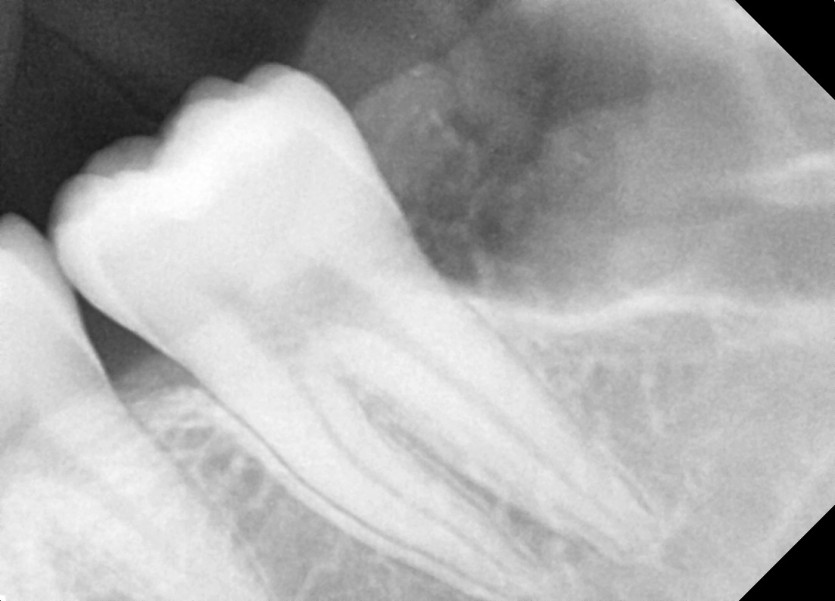

#38,48 사랑니 발치

구강 외과 전문의가 당일 발치했습니다.